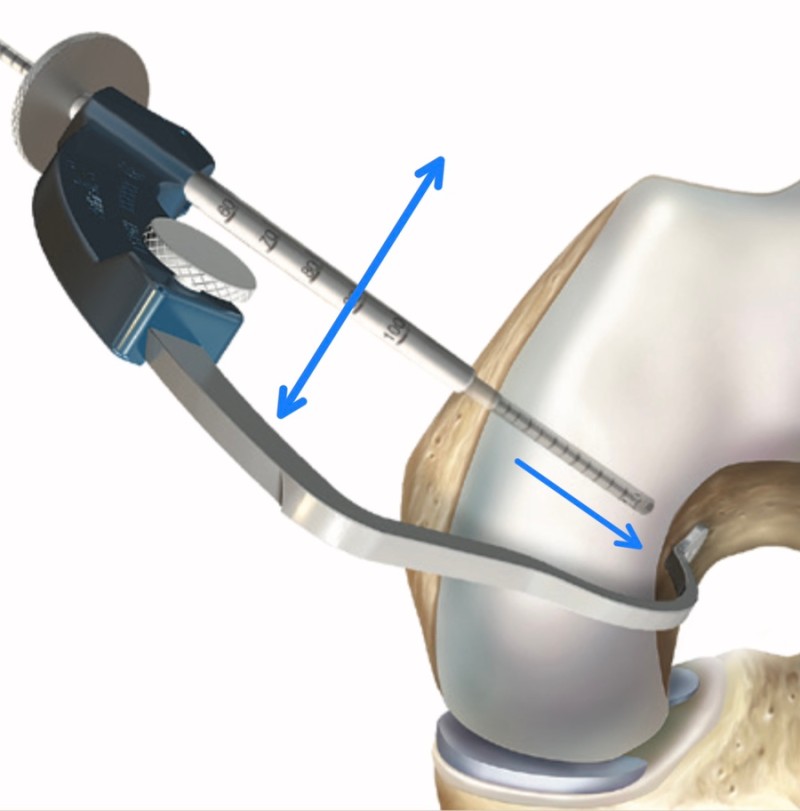

- 전내측 삽입구 술기 (AM portal technique)

경경골 술기를 통해 해부학적 위치를 정확하게

복원하기 어렵기 때문에, 이를 해결하기 위해 나온 방법이

전내측 삽입구 술기입니다.

경골 터널을 통하지 않기 때문에, 전내측 삽입구를 통해

전방십자인대가 무릎에 붙는 해부학적 위치에서 터널을

뚫을 수 있습니다.

- Outside-in 술기

전내측 삽입구 술기의 장점을(해부학적 터널 시작점)

살리면서도, 단점(터널이 짧아짐)을 해결하기 위해

특수하게 제작된 가이드를 사용하여,

바깥에서 안으로 터널을 만드는 방법이 고안되어

최근에는 가장 해부학적이고 안정적인 터널 길이를

확보할 수 있는 outside-in 술기가 많이 사용됩니다.